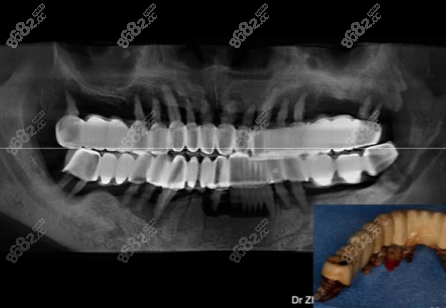

張叔叔戴全口烤瓷牙冠的片子▼

“后來烤瓷牙冠發(fā)黑,牙齦流膿還松動(dòng),不得不拆除,才有了做種植牙的打算,你還別說,這種植牙還真不錯(cuò),現(xiàn)在都六七年了,跟當(dāng)時(shí)剛種上使用的感覺居然是一樣的”